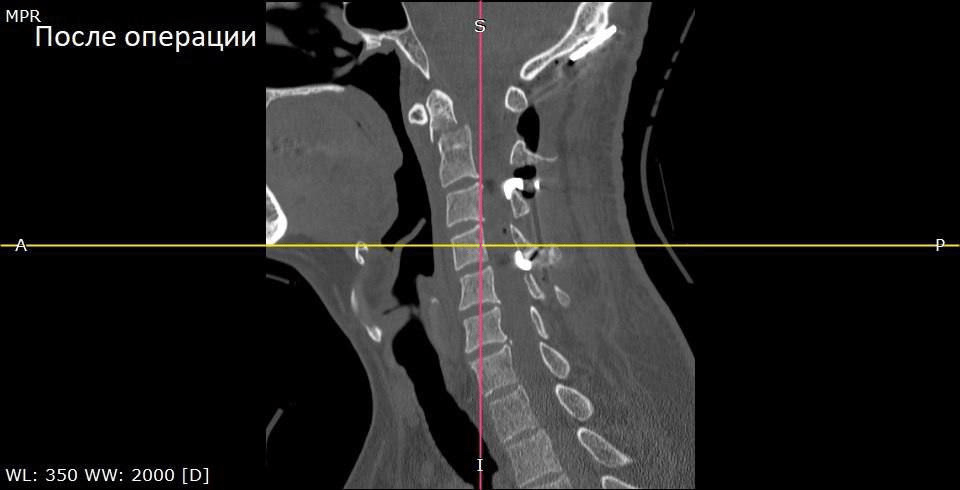

Мужчину госпитализировали. Врачи обследовали шейный отдел позвоночника и выявили перелом второго шейного позвонка (С2) со смещением отломка. Специалисты решили провести операцию — окципитоспондилодез («закрепление повреждённых позвонков верхнего шейного отдела. Позвонки и кости черепа соединяют в единый блок с помощью специальных креплений». — Прим. «Ё!»).

Фото: БУЗ ВО ВГК БСМП № 1

Вскоре пациент почувствовал лучше и даже смог сесть в жестком ортопедическом воротнике. Его выписали на четвёртые сутки после операции.